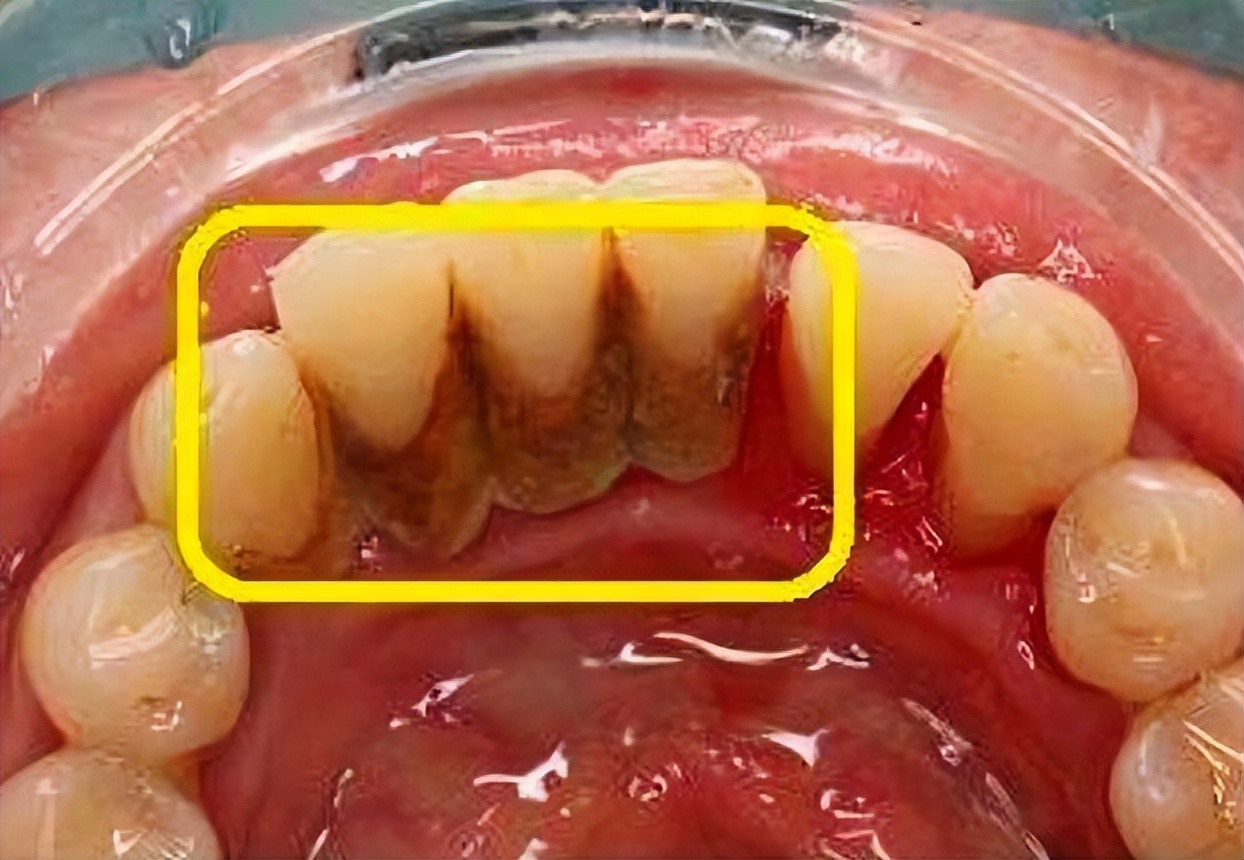

早上起来刷牙时,突然发现围绕牙齿周围有一团不明【黄黄黑黑的物体】,看起来脏脏的,不禁疑惑牙齿是出现什么问题了吗?经过多方查询,才发现原来这叫做【牙结石】呀。

牙结石长期得不到清洁,很容易变成黑色,影响牙齿美观,甚至是一些人一张开嘴巴,就有一股【难以言说】的味道……